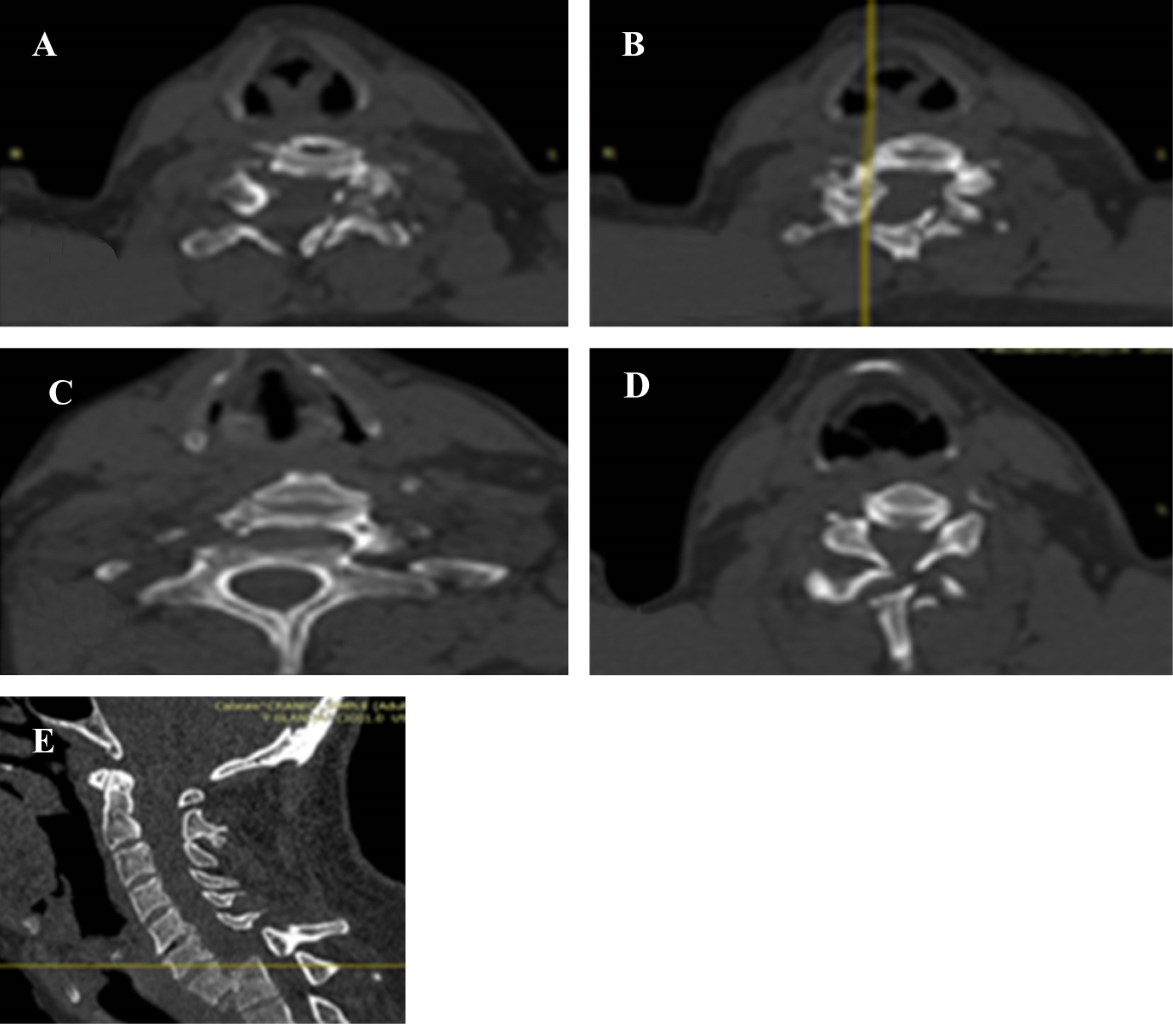

Se realiza serie traumática encontrando en la proyección AP de columna cervical (Figura 1A y B) incongruencia anatómica con un ángulo de lateralidad marcado (Figura 1C). Proyección lateral C1-C6 (Figura 2). TAC cráneo fractura de ambas láminas de C6 fractura de faceta inferior izquierda ipsilateral (Figura 2A y B) luxación de C7 sobre T1 (Figura 2C). Fractura de la plataforma superior de T1 más desplazamiento de 100% del cuerpo vertebral de C7 sobre el cuerpo vertebral de T1 (Figura 2C y D). Angiotomografía (Figura 3) realizada permitió descartar lesiones en vasos supraaórticos y descartar variantes que complicaran la realización del abordaje.

Se programa primer tiempo quirúrgico para realizar hemicorpectomía C7, discectomía C7-T1, espondilodesis con placa anterior dos niveles C6-C7, C7-T1, más toma y aplicación de injerto de cresta ilíaca, se corrobora resultado mediante TAC. Se realiza segundo tiempo quirúrgico siete días posteriores de primera intervención realizando abordaje cervical posterior + fascetectomías de C7 + fijación transfacetarias C6 y transpedicular de T1 con tornillos, barras y un cross-link (Figura 4).